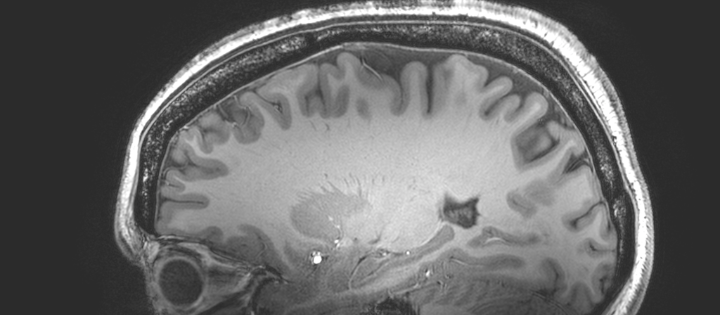

Black and white image of a brain

University’s largest ever funding award for UK’s most powerful MRI scanner

£29 million national scanning facility will help the UK lead the world in ultra-high field imaging to transform understanding of the brain and treatment of disease